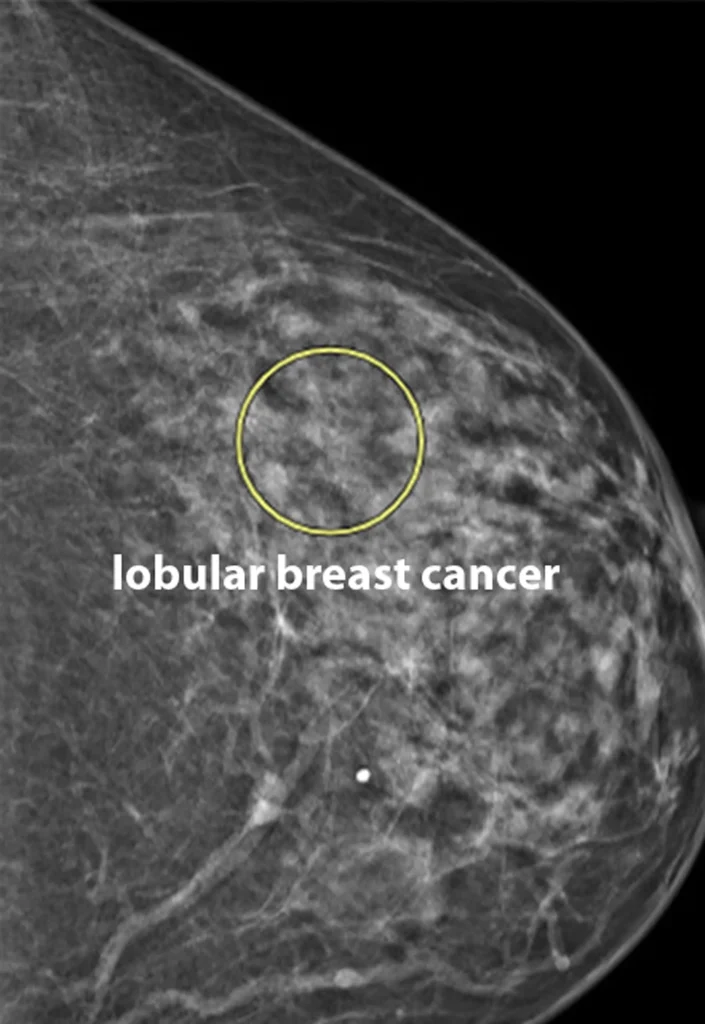

I was shocked to learn how different lobular breast cancer is from the more common ductal type. It doesn’t usually form solid lumps. Instead, it spreads in thin, web-like patterns that don’t always show up on imaging until later stages. That’s why doctors sometimes call it “the sneaky cancer.” Knowing I could’ve missed it for another year still chills me.